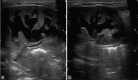

Epidermolysis bullosa (EB) is a rare, inherited, bullous disorder of the skin that occasionally involves the urinary tract. We report a 3-month-old, premature infant with EB, who presented with gross hematuria. Urine analysis revealed macrohematuria and proteinuria. The urine culture was negative. On ultrasonic evaluation, there was bilateral hydronephrosis and the distal ureters had echogenic shadows, suggestive of clotted blood. This case is consistent with the rare involvement of the urinary tract with hydronephrosis and bullous lesions.